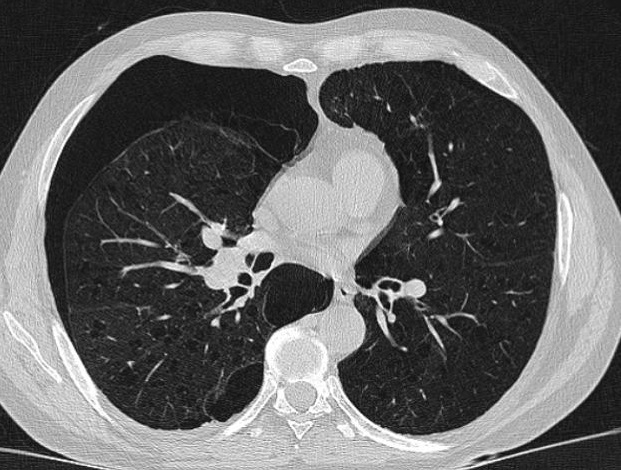

Aspect radiologique de même

cas avec image de collabe du poumon droit , le

mediastin devie vers à gauche . On peut en s'observe

la limite hyperdense de la plevre visceral du poumon

droit tres nette et facilement . Image radiologique

TDM en coupe axial fenetre parenchymateuse |